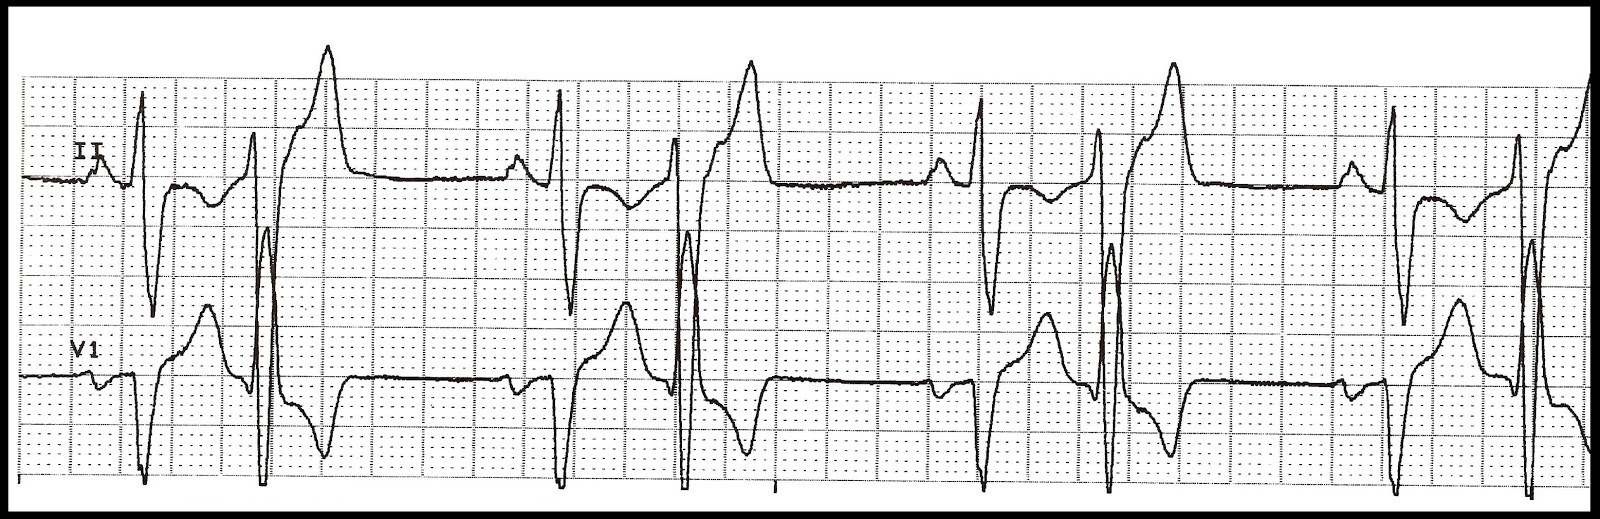

01. Identify the following rhythm.

10. Ventricular tachycardia